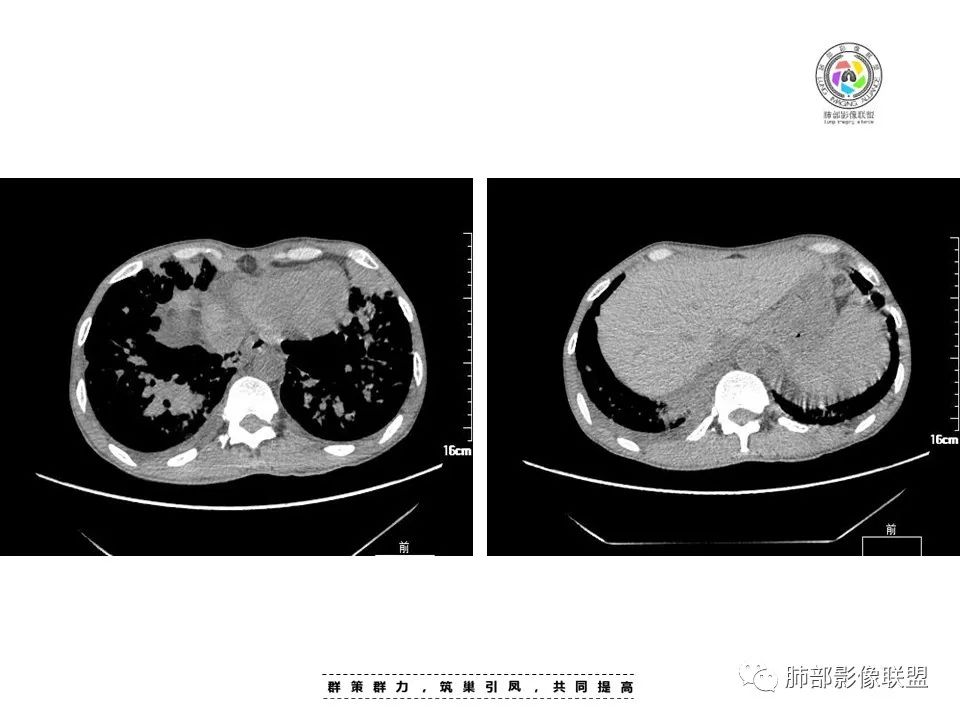

中年男性,发热、纳差、乏力、皮疹1月,,全身散在暗紫色丘疹,CD4明显减少,双肺散在多发斑片状、结节状密度增高影,边缘稍模糊,以双肺下叶较多,沿支气管血管束播散征象,小叶间隔增厚,叶间裂及双重胸膜腔少量积液,考虑马尼可能大,建议真菌,比如曲霉?念珠菌等

两肺多形态小斑片影,上轻下重沿支气管血管分布,双肺下叶小片状,密度不均匀,含模糊的GGO影,右肺中、下叶与左肺舌叶及下叶病灶累及中轴及小叶间隔增厚,双肺叶间胸膜增厚及伴随粟粒结节,双侧胸腔对称性少量积液,纵隔脂肪间隙混浊(示淋巴回流受阻),慢性发病,发热,乏力,皮肤皮诊表现,贪血,WBC,CD4+低,脾增大,肺感染疾病:马尔尼菲篮状菌,并发TB待排,支气管镜肺泡灌洗液和结核X-Pert检查。

两肺弥漫性性结节状、小片状及片状带晕的病灶,煎蛋征、点晕征,主要分布两肺中下叶,病灶周围小叶间隔增厚呈网格状影,部分病灶累及胸膜,伴两侧胸膜增厚。

2.本例双肺小叶间隔增厚明显,多发结节影及片状实性密度影,沿血管支气管束分布为主,两侧较为对称,病灶多环以磨玻璃晕,边界不清。

双侧胸腔少量积液。双肺门及纵隔未见明确肿大淋巴结,纵隔结构间隙模糊。

3.有学者将这种具有沿双肺支气管束分布的实性密度片影描述为“火焰征”,认为具有一定特征性,单就影像表现而言,这种影像表现也可以见于其他病损或多种病理改变的叠加。